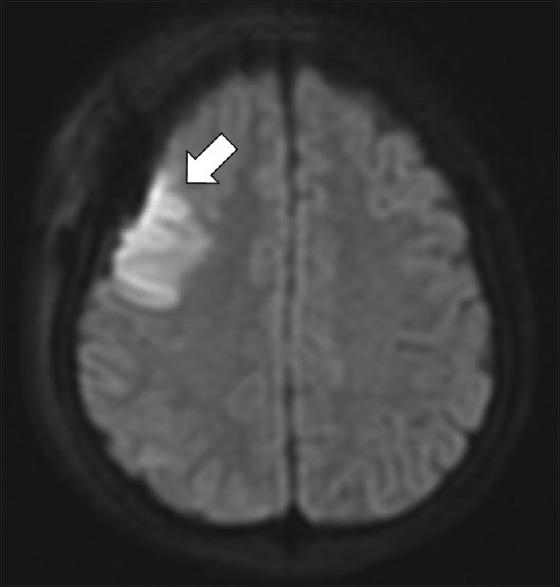

并存烟雾病综合征和1型糖尿病:一例报告及文献复习

Coexisting Moyamoya Syndrome and Type 1 Diabetes Mellitus: A Case Report and Review of the Literature.

烟雾病(MMD)是一种尚未被完全理解的疾病,影响多个年龄组,主要呈双峰年龄分布。我们报告一例1型糖尿病(1型DM)与烟雾病相关的病例,并对现有文献进行综述。我们发现五篇论文描述了这种关联,形式包括一篇病例报告、一篇病例系列和三篇回顾性综述。尽管对潜在的病理生理学了解不足,但自身免疫性疾病与烟雾病之间似乎存在明确关联。对于这类患者进行管理的临床医生,当1型DM的年轻患者出现新发神经症状时,应保持警惕并高度怀疑。